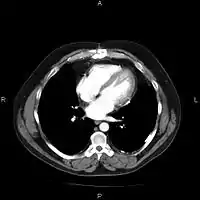

A picture archiving and communication system (PACS) is a medical imaging technology which provides economical storage and convenient access to images from multiple modalities (source machine types).[1] Electronic images and reports are transmitted digitally via PACS; this eliminates the need to manually file, retrieve, or transport film jackets, the folders used to store and protect X-ray film. The universal format for PACS image storage and transfer is DICOM (Digital Imaging and Communications in Medicine). Non-image data, such as scanned documents, may be incorporated using consumer industry standard formats like PDF (Portable Document Format), once encapsulated in DICOM. A PACS consists of four major components: The imaging modalities such as X-ray plain film (PF), computed tomography (CT) and magnetic resonance imaging (MRI), a secured network for the transmission of patient information, workstations for interpreting and reviewing images, and archives for the storage and retrieval of images and reports. Combined with available and emerging web technology, PACS has the ability to deliver timely and efficient access to images, interpretations, and related data. PACS reduces the physical and time barriers associated with traditional film-based image retrieval, distribution, and display.

Most PACS handle images from various medical imaging instruments, including ultrasound (US), magnetic resonance (MR), Nuclear Medicine imaging, positron emission tomography (PET), computed tomography (CT), endoscopy (ES), mammograms (MG), digital radiography (DR), phosphor plate radiography, Visible Light Photography (VL), Histopathology, ophthalmology, etc. Additional types of image formats are always being added. Clinical areas beyond radiology; cardiology, oncology, gastroenterology, and even the laboratory are creating medical images that can be incorporated into PACS. (see DICOM Application areas).